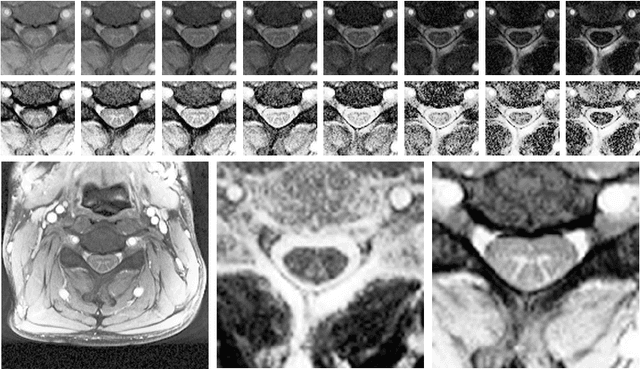

Abstract:The small butterfly shaped structure of spinal cord (SC) gray matter (GM) is challenging to image and to delinate from its surrounding white matter (WM). Segmenting GM is up to a point a trade-off between accuracy and precision. We propose a new pipeline for GM-WM magnetic resonance (MR) image acquisition and segmentation. We report superior results as compared to the ones recently reported in the SC GM segmentation challenge and show even better results using the averaged magnetization inversion recovery acquisitions (AMIRA) sequence. Scan-rescan experiments with the AMIRA sequence show high reproducibility in terms of Dice coefficient, Hausdorff distance and relative standard deviation. We use a recurrent neural network (RNN) with multi-dimensional gated recurrent units (MD-GRU) to train segmentation models on the AMIRA dataset of 855 slices. We added a generalized dice loss to the cross entropy loss that MD-GRU uses and were able to improve the results.